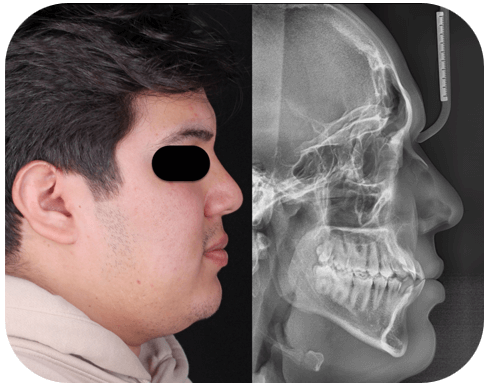

Análisis radiográfico

La radiografía lateral de cráneo en el análisis de Ricketts arrojo una convexidad de -0.01 mm y altura facial inferior de 47.85º mostrando una relación intermaxilar Clase I. Dentalmente presenta una Clase III molar, proinclinacion dental (L1-A-Po: 35º) angulo interincisal (111º), biotipo mesofacial con crecimiento vertical. Un IMPA: 100º en Tweed.

En la radiografía panorámica se observa simetria de las ramas mandibulares, presencia de 32 OD erupcionados, obstruccion parcial de la fosa nasal izquierda y seno maxilar izquierdo reducido.

Fig 4. Radiografia lateral de craneo inicial